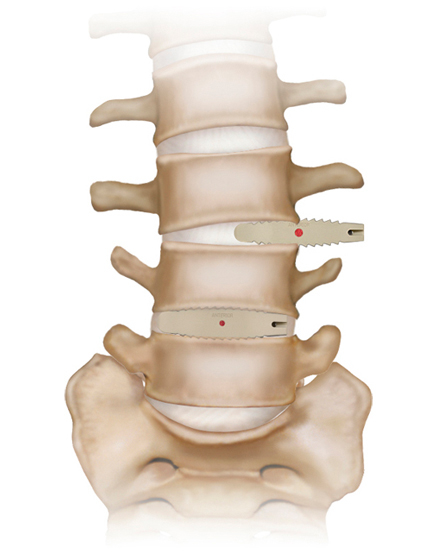

低侵襲脊椎側方固定術 XLIF (エックスリフ)、OLIF(オーリフ)

適応となる疾患:腰椎椎間板ヘルニア、腰部脊柱管狭窄症、腰椎変性すべり症、腰椎変性側弯症など

日本では2013年から承認されている低侵襲な脊椎側方固定術です。この手術は、トレーニングを受けた医師だけが実施できるため、全国でも限られた医療機関でのみ受けられます。当センターの日方医師は資格を有しているため実施可能です。この手術の最大の利点は脊髄神経を直接触らないで神経を圧迫から解除することにあります。側腹部に約5cmの皮膚切開により、下図のように神経機能を電気モニタリングで随時確認し重要な神経を避けながら椎間板内に人工骨を移植します。その後、腰部から固定術を行います。翌日から起立・歩行が許可され、入院期間は通常10~14日程度になります。